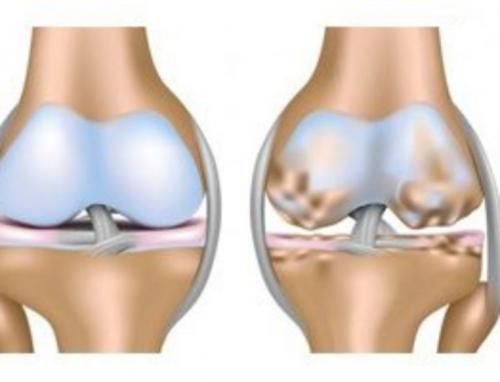

- Первая стадия. Является наиболее скрытой и незаметной, поскольку не несет в себе выраженных симптомов и практически не имеет визуальных подтверждений. На ранней стадии артроза пациент может ощущать слабую боль при интенсивных нагрузках и периодическое воспаление пораженной области. Однако это не отменяет того факта, что в суставах уже начинаются дегенеративные процессы, затрагивающие суставную жидкость.

- Вторая стадия. Если артроз переходит в следующую стадию, это указывает на начало разрушения суставной структуры. Также в поврежденной анатомической области появляются наросты, а боль серьезно усиливается. При движении в суставах ощущаются хруст и выраженная боль.

- Третья стадия. Считается самой опасной и трудноизлечимой. При ней хрящевая ткань сильно истончается, а при внешнем осмотре можно заметить очаг разрушения. Трудоспособность пациента оказывается под угрозой.

Поскольку первые две стадии не считаются хроническими, поскольку они не несут серьезных патологических изменений, врачи делают следующий вывод: при артрозе 3 степени инвалидность положена.

Гонартроз коленного сустава 3 степени характеризуется утратой полноценного движения. Остаются только покачивания пораженным суставом. Он очень сильно деформируется. После рентгена можно увидеть отсутствие суставной щели. Сама поверхность расширена из-за разрастания ее краев. Деформирование остро выраженное, имеется уплотнение обоих эпифизов.

Третья стадия , это артроз декомпенсированного вида, который может быть двух видов , с реактивным синовитом вторичного типа и с болевыми ощущениями.